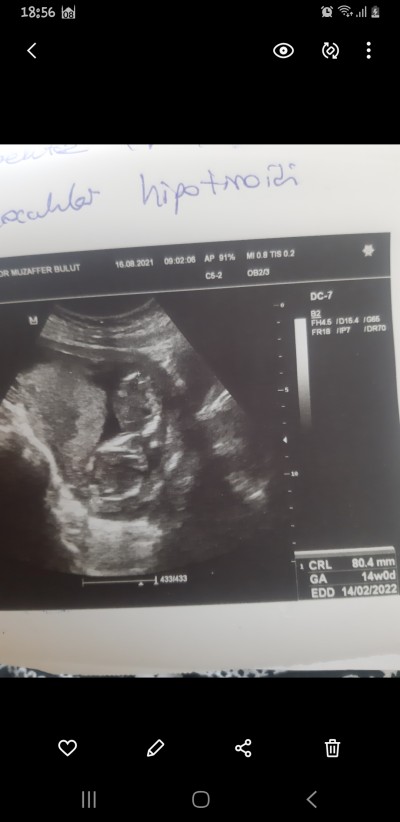

Cinsiyet tahminiii

Cinsiyet tahmini

Erkek canım:))

Allahım ilk önce sağlıklı hayırlı bir erkek evlat nasip etsin istiyorum zaten bakalım iki defa erkek çocuk rüyanda gördüm ilk defa hamileligimde rüya gordum